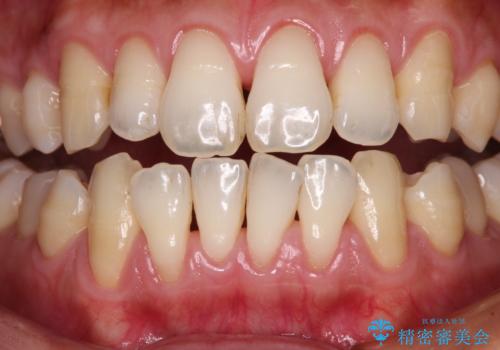

- 年々歯肉退縮が進行することを気にして来院された患者様です。

歯肉が菲薄であることが経年的な進行の原因であることが推察されたため、上顎からの結合組織移植術(CTG)により、歯根の被覆を行うとともに、歯肉の厚みを増すことで将来の退縮リスクを抑制することとしました。

上顎両側から歯肉を採取したたため、術後は痛みや出血で辛い思いをされましたが、1回の処置で満足のいく結果となりました。

根面被覆量も改善できましたが、歯肉の厚みが十分なものとなったことで、今後の歯肉退縮に歯止めをかけることができました。